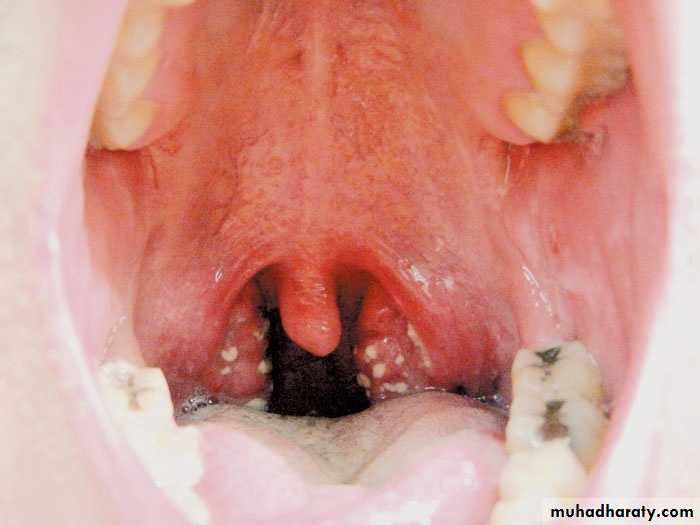

Gingival hypertrophy

Clinical images

Black hairy tongue

Geographic tongue (benign migratory glossitis)

Fissured Tongue

Herpetic glossitis

Beefy red tongue